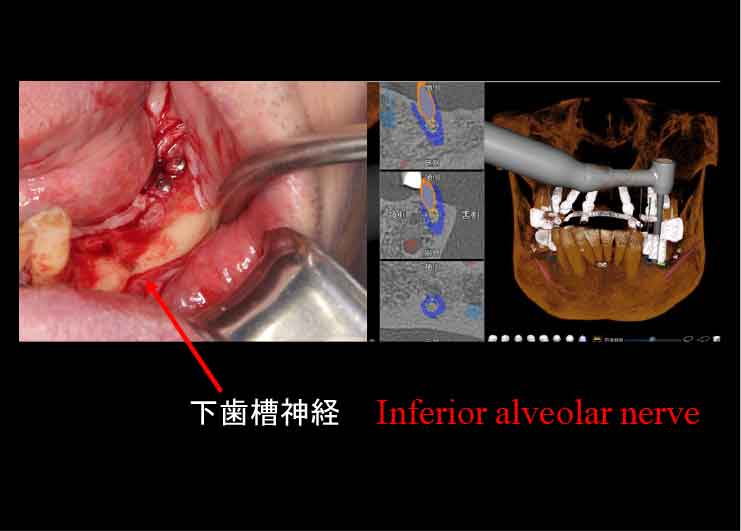

下歯槽神経近くにインプラントを埋入したケース。

歯を失った下あごの骨が大きく吸収し、下歯槽神経の出入り口であるオトガイ孔が表面に近い部分に出てきています。そこで、X-ガイド使用により、下歯槽神経を避けた手術を行いました。

CTスキャンを撮影後、下歯槽神経の位置を明示した3D模型を作製。

DTX Studioで、下歯槽神経の位置とインプラントの埋入方向、深度を詳細に検討し、神経にダメージを与えないインプラントの位置をシミュレーション、X-ガイドによるナビゲーション手術を行いました。

DTX Studioで、下歯槽神経の位置とインプラントの埋入方向、深度を詳細に検討し、神経にダメージを与えないインプラントの位置をシミュレーション、X-ガイドによるナビゲーション手術を行いました。